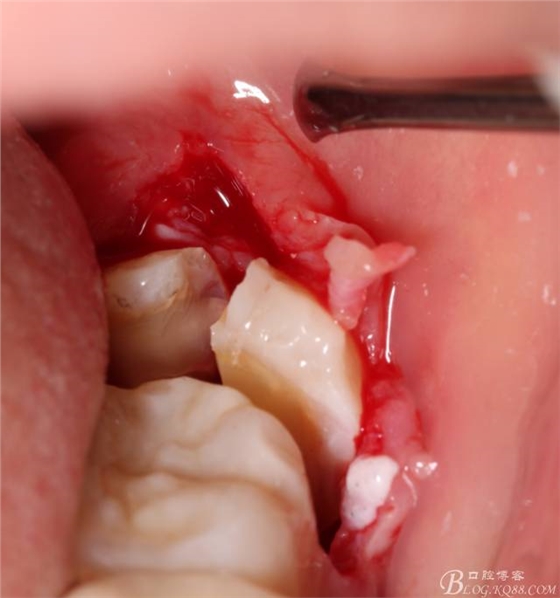

切開:角形切口,這個(gè)位置切開我喜歡更易操作12#刀。

640 (8).jpg

640 (9).jpg

鈍性翻辨露冠

640 (10).jpg